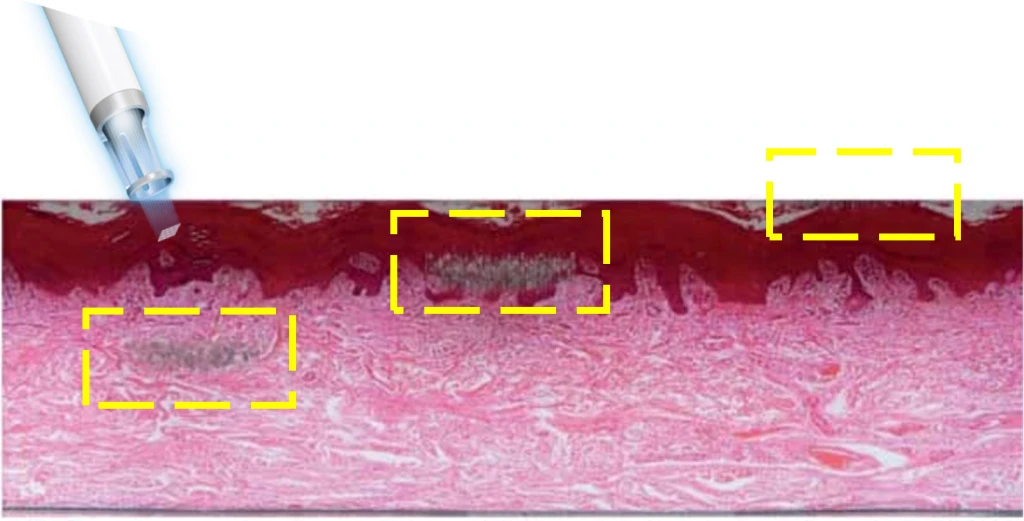

Клинически доказанный LIOB (лазеро-индуцированный оптический пробой). Лазерный луч оказывает фотомеханическое воздействие без термического эффекта (нагрева), создаются зоны микротравм, представленные в виде дермальных вакуолей, что стимулирует процесс заживления и приводит к омоложению кожи.

Гистология образцов кожи морской свинки (H&E, 200X).

а - Внутридермальный LIOB с помощью Dia FX глубиной 1064 нм. I (130 МДж, 3 Гц),

b - Внутридермальный LIOB с помощью Dia FX 1064 нм Lv. II (130 МДж, 10 Гц)